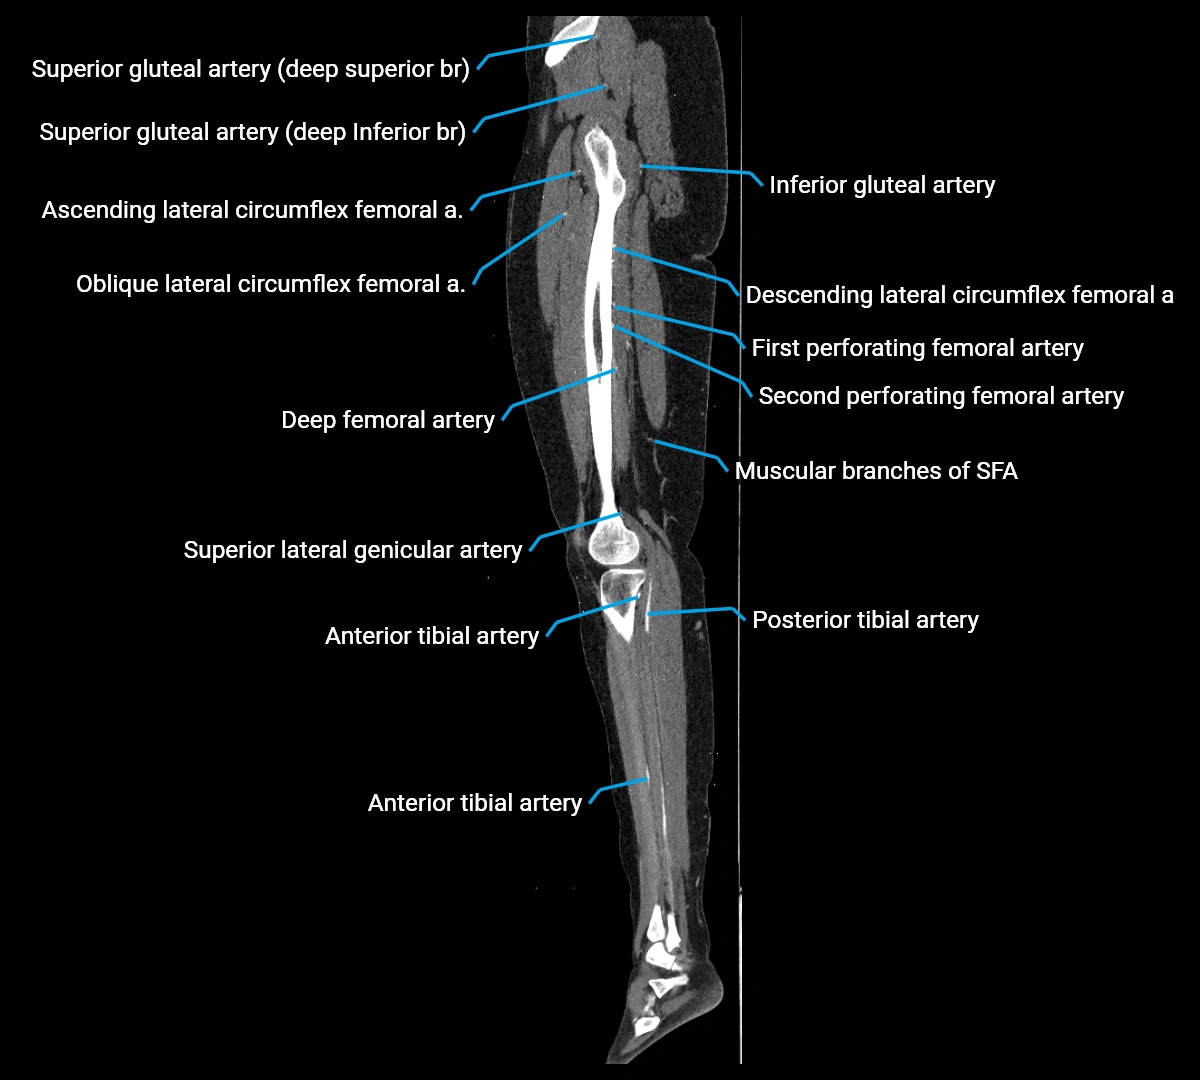

Contrast-enhanced CT (CTA):

• Gold standard for abdominal aortic imaging

• Provides excellent detail of lumen, wall, aneurysm, thrombus, and branch vessels

• Multiplanar and 3D reconstructions help in aneurysm measurement, stent graft planning, and dissection evaluation

• Detects acute rupture, traumatic injury, or occlusion with high sensitivity